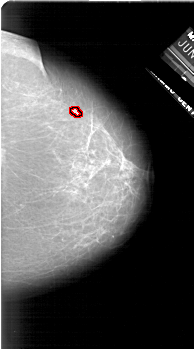

A_1624_1.RIGHT_MLO

RIGHT_MLO LINES 6091 PIXELS_PER_LINE 3091 BITS_PER_PIXEL 12 RESOLUTION 43.5 OVERLAY

FILE: A_1624_1.RIGHT_MLO.OVERLAY

TOTAL_ABNORMALITIES 1

ABNORMALITY 1

LESION_TYPE MASS SHAPE LOBULATED MARGINS OBSCURED

ASSESSMENT 4

SUBTLETY 2

PATHOLOGY MALIGNANT

TOTAL_OUTLINES 1

BOUNDARY